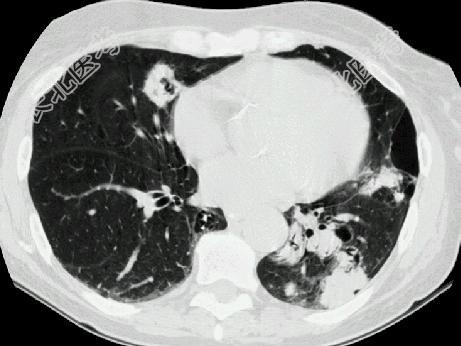

- 单项选择题多发性骨髓瘤患者出现咳嗽,咳痰, 气急,胸片检查发现病变后行CT检查如图, 最可能的诊断为 ( )

A、肺部感染

B、两肺结核

C、骨髓瘤转移肺部

D、肺淀粉样变性

E、肺转移瘤